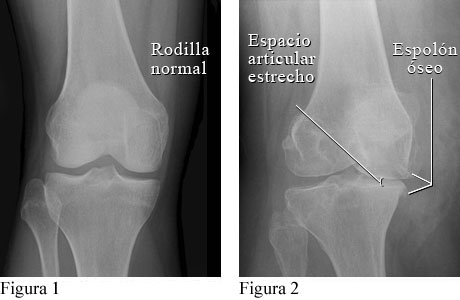

La figura 1 es una radiografía de una rodilla normal con espacio normal entre los huesos de la parte superior y de la parte inferior de la pierna. La figura 2 muestra espolones óseos y un estrechamiento del espacio articular causados por osteoartritis.